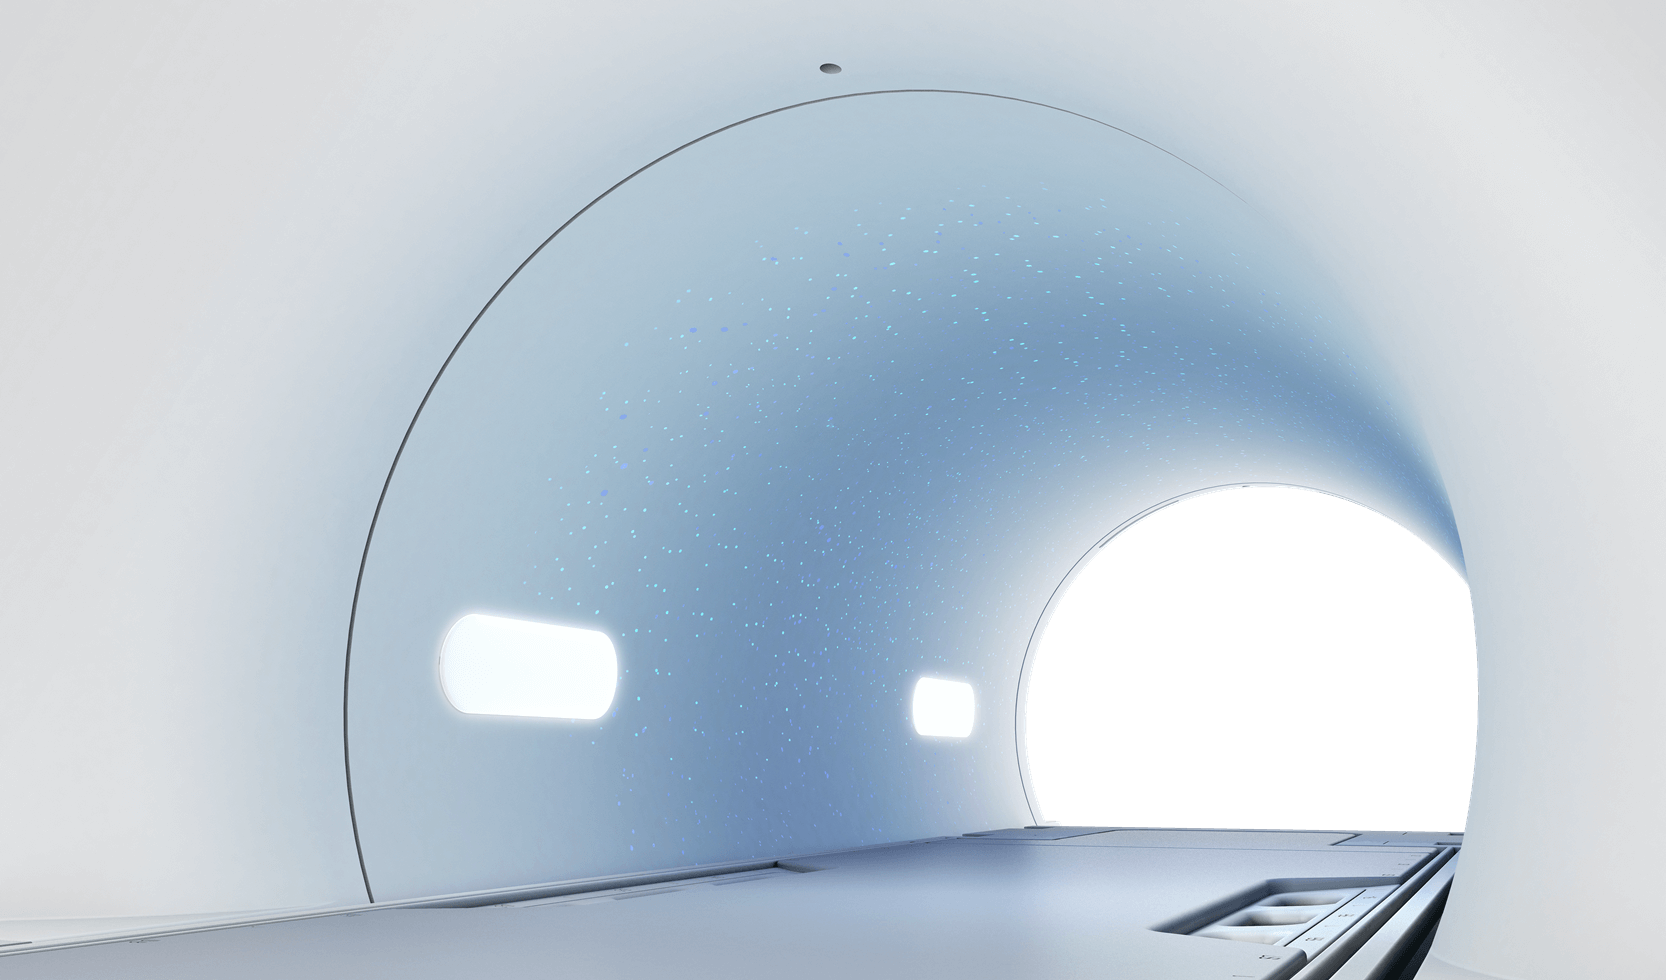

业界首创星空光环境

扫描床推进,星光点亮,受检者仿佛置身于银河,舒缓紧张情绪,让磁共振检查转化为沉浸式的“瞻星”体验。